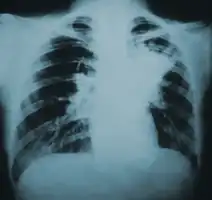

Chest X-ray